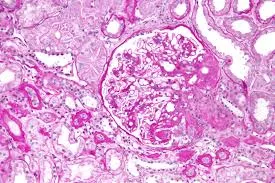

A glomerulonefrite por C3 (GNC3) resulta de ativação descontrolada da via alternativa do complemento e pode simular uma GN pós-infecciosa. O diagnóstico correto depende do reconhecimento do padrão de deposição de C3 e da investigação genética. Com terapias-alvo como o eculizumabe e o iptacopan, identificar precocemente a GNC3 pode mudar o desfecho do paciente.

Luís Sette

9 meses atrás